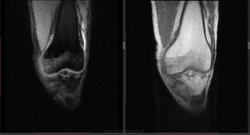

Мужчина 1963 г.р. Жалуется на боль в левом коленном суставе около 6 мес, в последний месяц стало совсем тяжко. Со слов заболел зимой, когда во время прогулки коленки сильно замерзли. Сам думаю на асептический некроз, но смущает множественность поражения.

Дмитрий, я в заболеваниях суставов не дока, но трабекулярный отек вкупе с выпотом может быть обусловлен воспалительными изменениями , но полностью начальные проявления аваскулярного некроза не могу отрицать.

я бы не поставил аваскулярный некроз. если исключена травма, дифференцировать с артритом.

Хрящ не поврежден, для артрита...